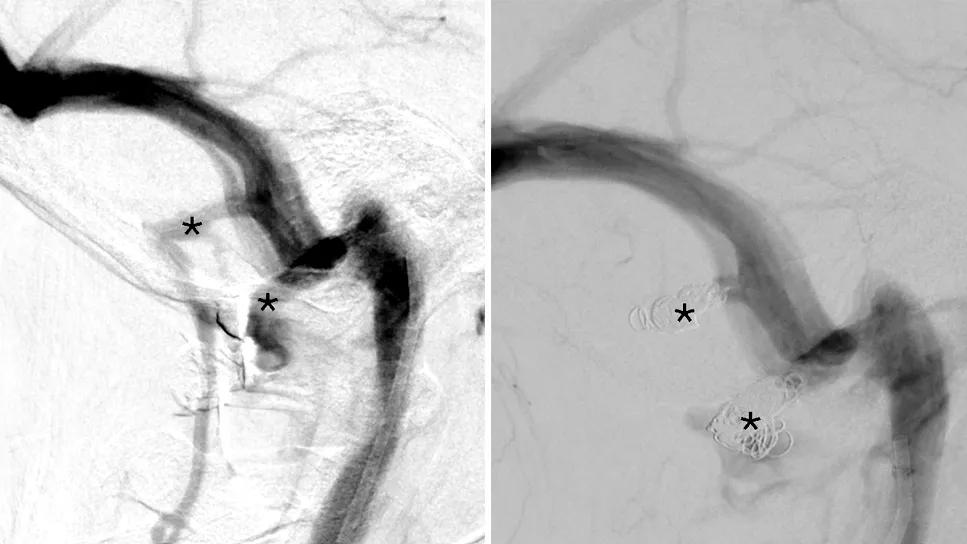

side-by-side scans of a vein in the brain

Lateral digital subtraction angiograms in the venous phase show mastoid and condylar emissary veins (asterisks) before (left image) and after (right image) coil embolization in the case patient. The mastoid and condylar emissary veins provide accessory drainage from the sigmoid sinus across the skull to the paraspinal venous plexus.